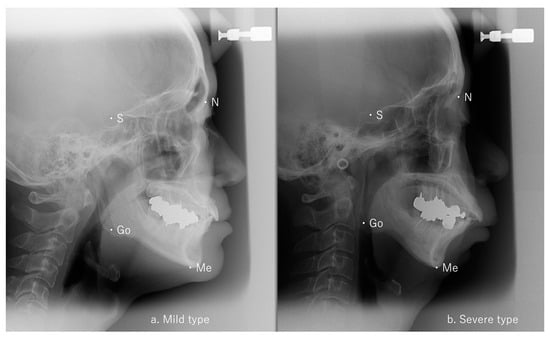

2.2. Cephalometric Analysis

3.1. Relationship Between Ricketts Analysis and Maxillofacial Morphology in OSA Patients